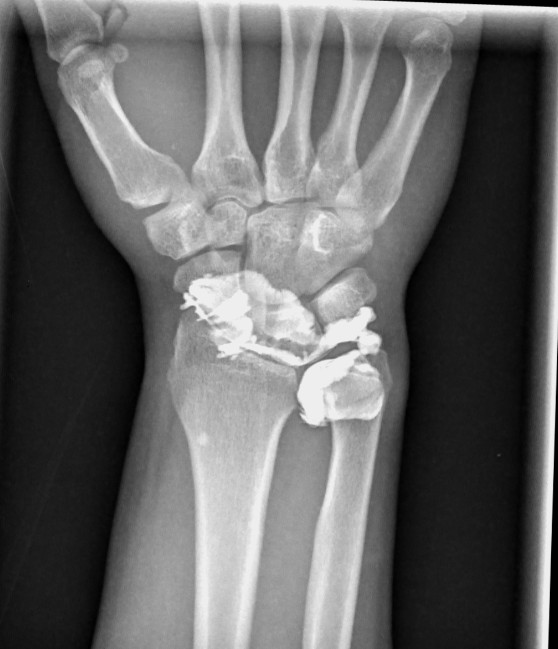

JuanMiranda@themskarchive·

26/11/2025.🖐️37M with central dorsal wrist pain. US-guided arthrography showed immediate contrast passage from RC into the MC joint → intrinsic ligament tear. 📸 CT & MR arthrograms confirmed complete lunotriquetral ligament rupture #MSK #Radiology #SLIL #WristPain #MRI #CT🩻

JuanMiranda tweet mediaJuanMiranda tweet mediaJuanMiranda tweet media